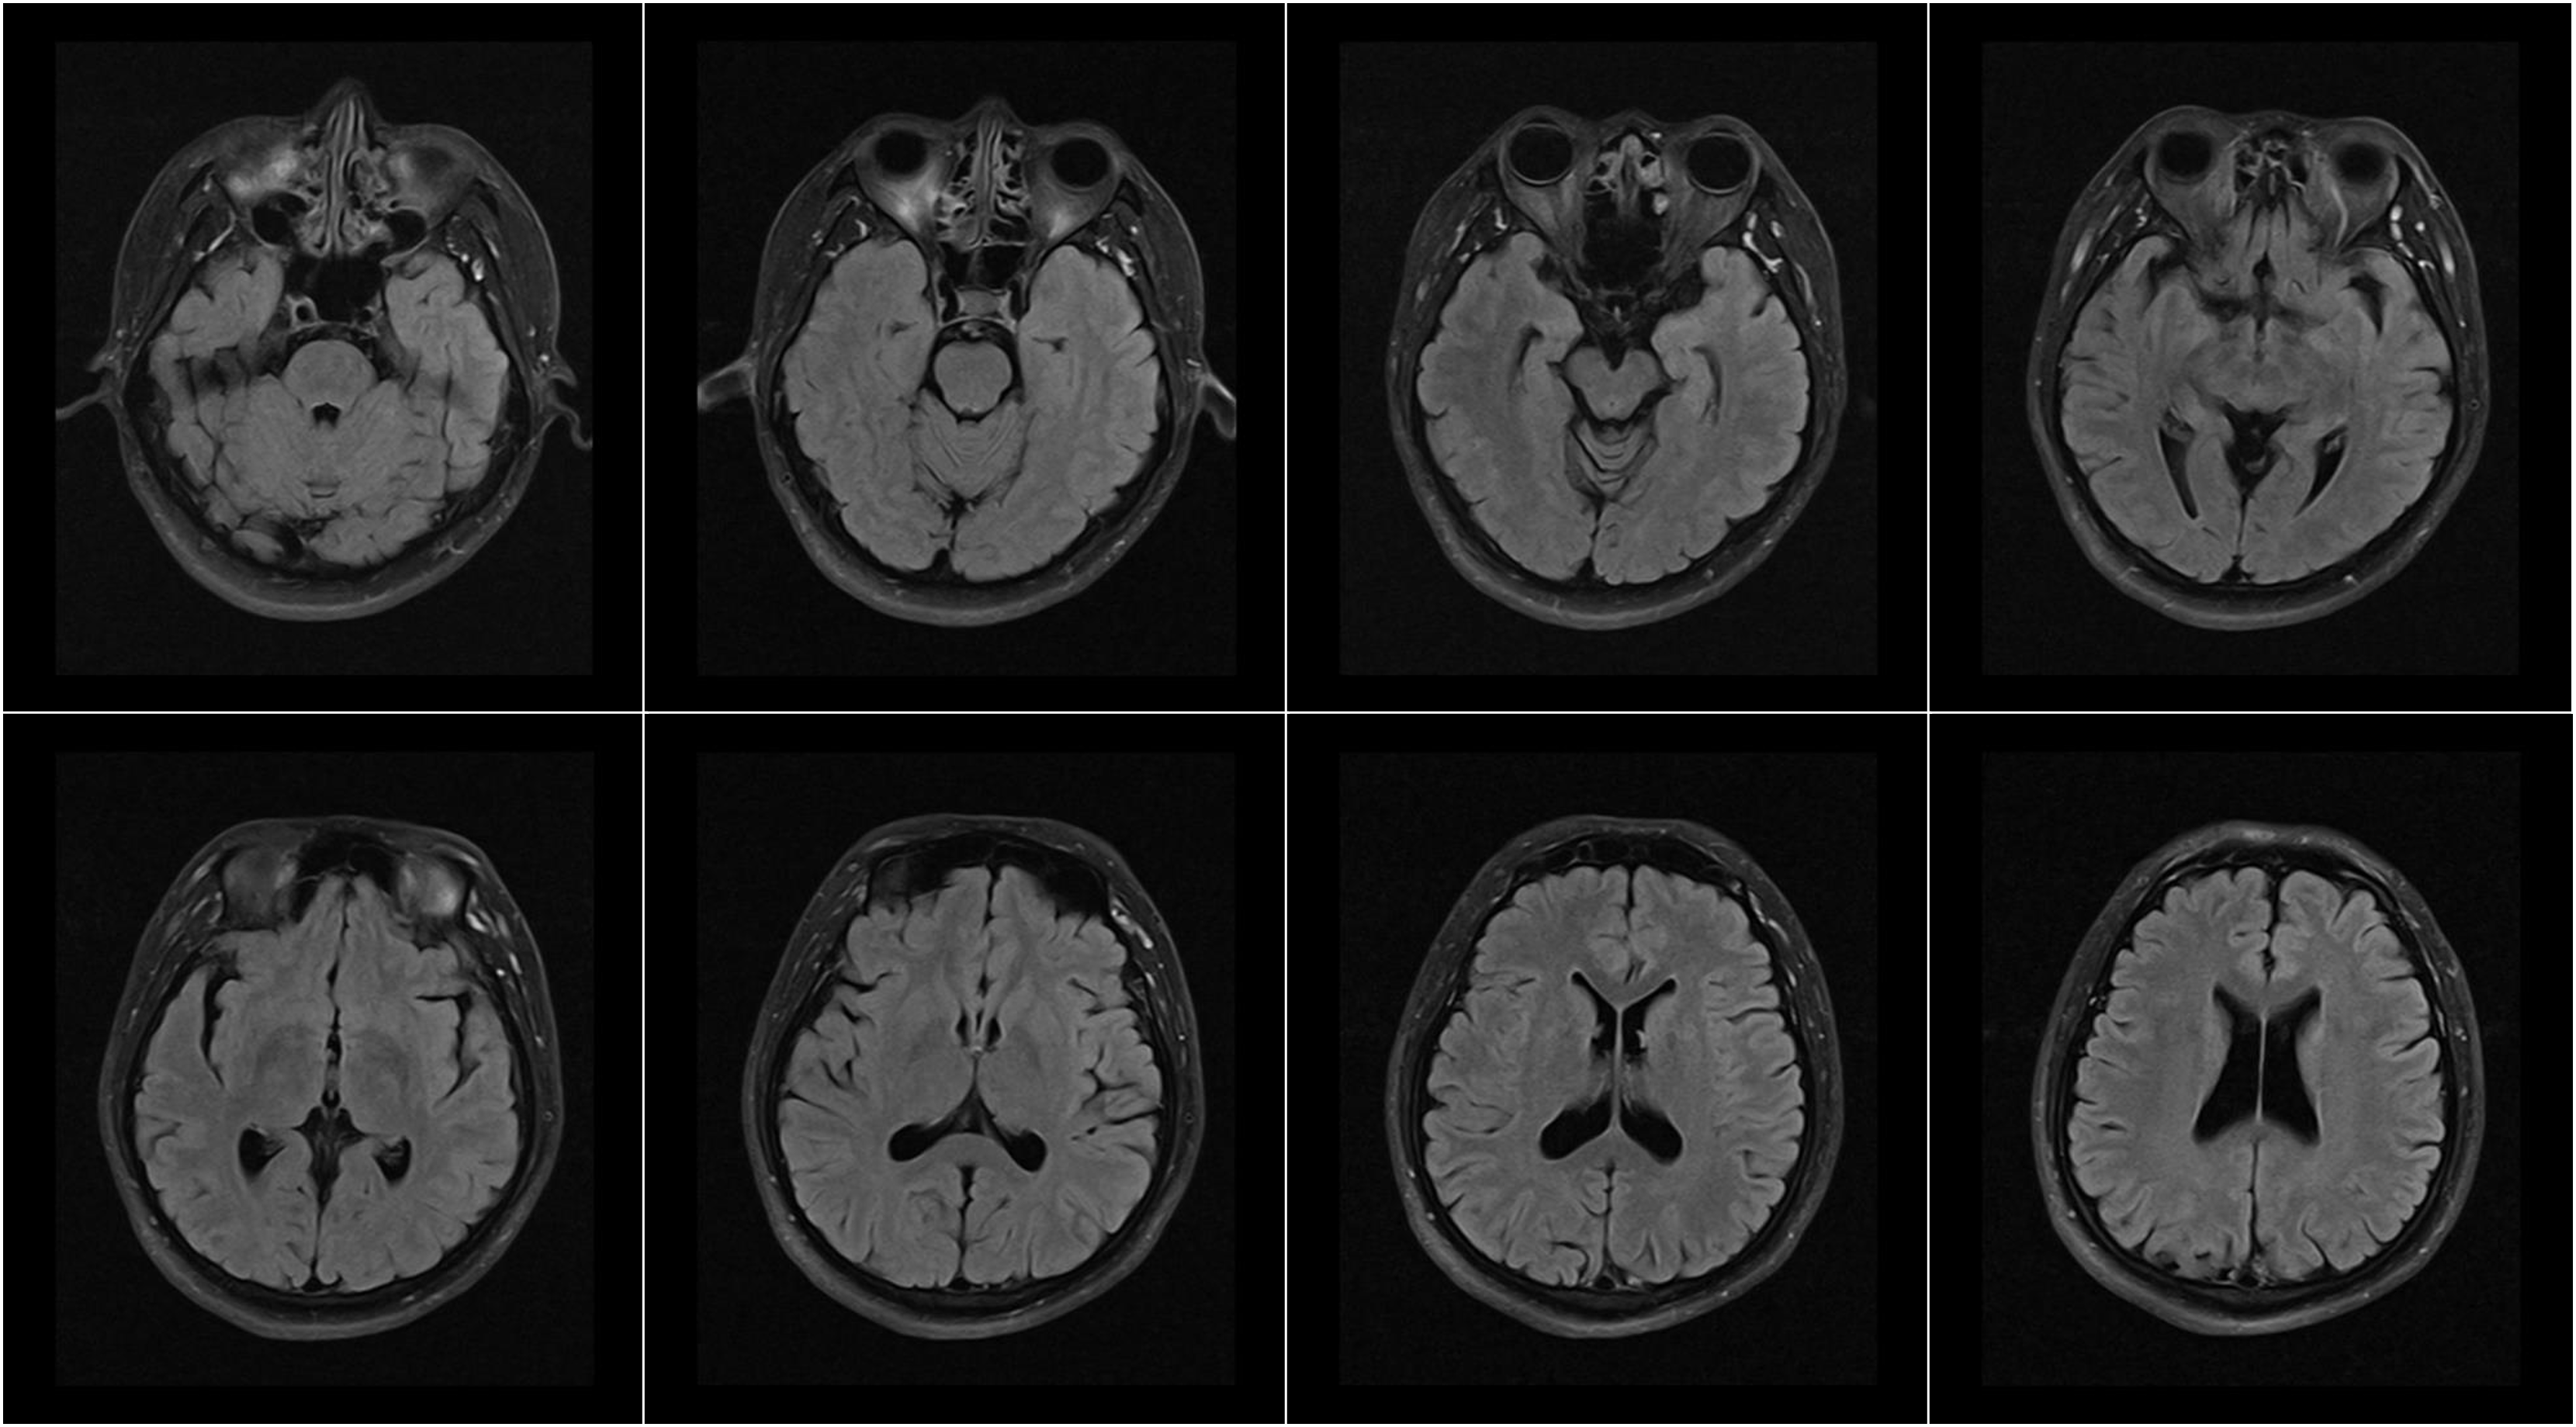

Hình ảnh lâm sàng